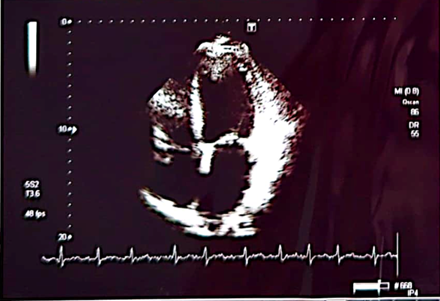

Control echocardiogram is performed

We can appreciate the amazing size left ventricle and normal global and segmental contractility with normal left ventricular ejection fraction (75%). Previous 10%. In addition, the patient was asymptomatic from the cardiological point of view. In such a way that all the medication that was started for the treatment of dilated cardiomyopathy was suspended, such as: Sacubitril/valsartan, furosemide, aldactone, ivrabadine, metoprolol, oral anticoagulants. The only treatment for her arterial hypertension was left with candesartan 16 mg per day and rosuvastatin 40 mg at night for mixed dyslipidemia. The following 6 patients 5 are male with ages: 28, 33, 35, 85 and one female: 95 years of age whose ejection fractions were similar 18, 17, 16 and 15% respectively and their evolution is similar to that of First case with an echocardiographic and clinical evolution to total normality. All patients currently lead a completely normal life.1-3